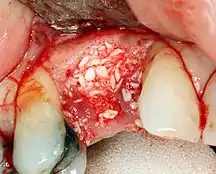

تطعيم (ترقيع) العظام ضروري عندما يكون هناك نقص في العظام كما أنه يساعد على استقرار الغرسة في مكانها علي المدي الطويل وتقليل فقدان مستوى العظام في الهوامش. لتحقيق عرض وارتفاع كافيين للعظم، تم تطوير العديد من تقنيات تطعيم العظام. فترقيع العظام يتم بملء العيب إما بالعظام الطبيعية المحصودة أو بديل عظمي صناعي، مغطى بغشاء شبه نفاذ ويسمح له بالالتئام. و خلال مرحلة الشفاء، يستبدل العظم الطبيعي العظم المستخدم في الترقيع ليشكل قاعدة جديدة للغرسة.[30] في حين أن هناك دائمًا أنواع جديدة من الغرسات، مثل الغرسات القصيرة (ذات القطر المنخفض)، وتقنيات للسماح بحلول وسط لوضع غرسات، فإن هدف العلاج العام هو أن يكون الحد الأدنى لارتفاع العظم 10 مم، وعرض 6 مم.[31]

هناك ثلاثة إجراءات شائعة للبناء وهي:[32]

- تكبير(ترقيع) جانبي (زيادة العرض)

- تكبير(ترقيع) رأسي (زيادة الارتفاع)